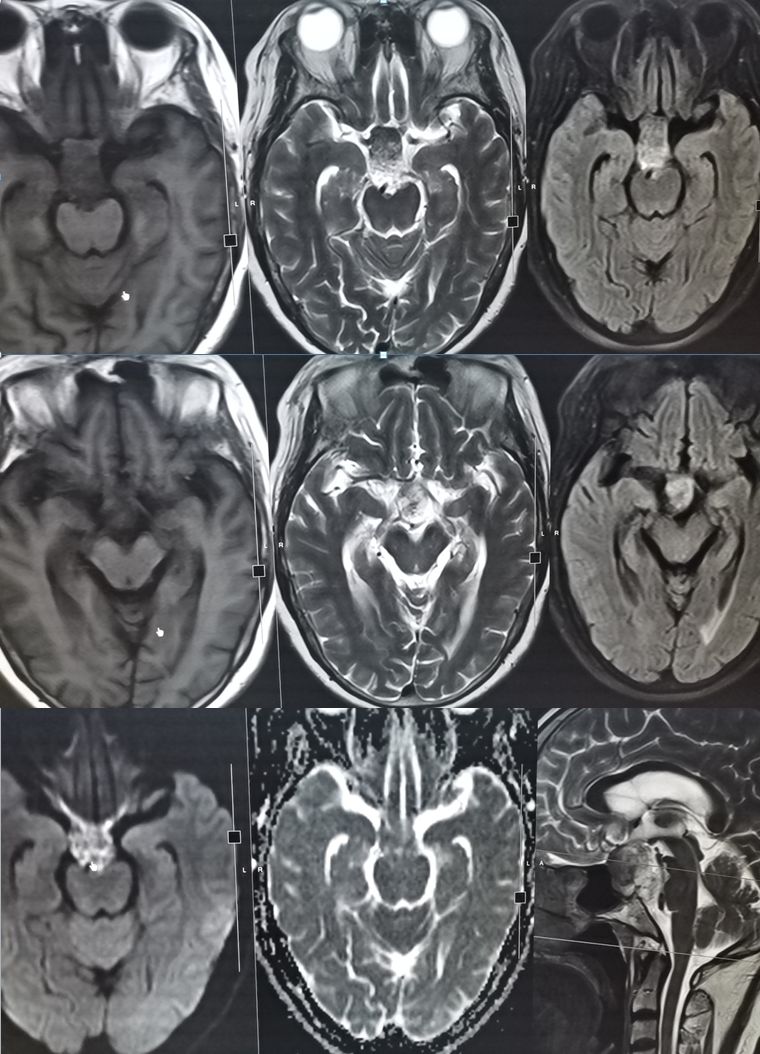

男,29岁,言语不清,协调不良以及行走不平衡3周。

答案:*洛因海**海绵状白质脑病。*洛因海**海绵状白质脑病(heroin spongiform leukoencephalopathy,HSLE)是因烫吸或静脉注射*洛因海**而引起的中枢神经系统器质性疾病。临床和影像特点如下:

1. 有吸*洛因海**史;

2. 急性或亚急性起病;

3. 小脑受损为首发症状,进一步加重可出现锥体系及锥体外系受损表现,甚至昏迷、去皮层状态,但感觉系统不受累;

4. CT和MRI影像显示病灶位于脑白质区,呈广泛、对侧性损害(小脑半球、脑干、内囊后肢、胼胝体压部及大脑半球后2/3),其中小脑受累严重,小脑中线两旁、边界清楚的对侧性类圆形或蝴蝶样病灶最具特点(蝶翼征);在脑干部位,若同时有红核及网状结构受累,则可见“蟹钳征”;在内囊后肢则呈“八字征”。病变在T1W为低信号,T2WI为高信号,FLAIR为高信号,且增强扫描一般无强化.5.病理显示脑白质空泡样变。